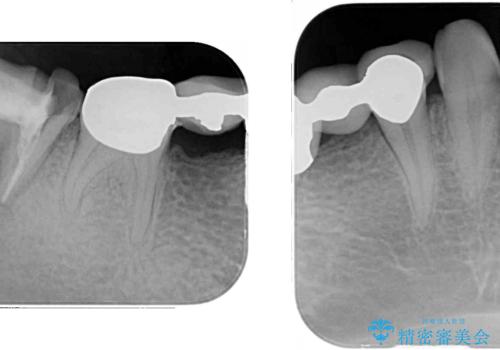

- 近医で奥歯が割れているので抜歯が必要と言われたとのことで来院された患者様です。

診断の結果、歯根が縦に破折しており抜歯が必要な状態でした。

抜歯してからインプラント埋入までには時間がかかるため、その間に下顎左右臼歯の金属のブリッジをオールセラミックへ変えていくこととしました。